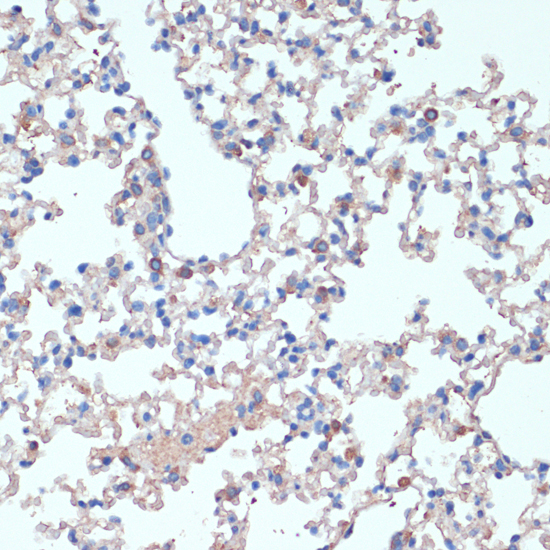

Immunohistochemistry of paraffin-embedded mouse lung using IL2 at dilution of 1:100 (40x lens).